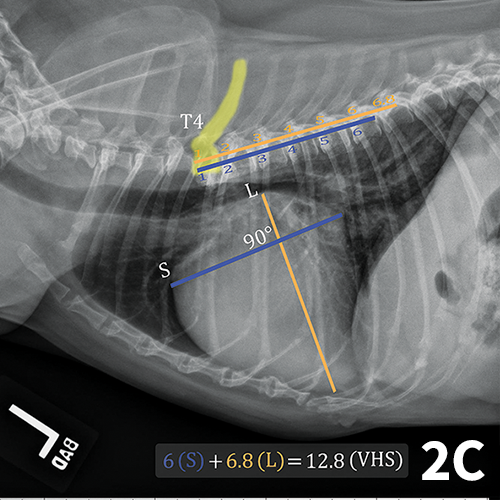

From www.vrogue.co

Vertebral Heart Score To Evaluate Cardiac Size In Tho vrogue.co Dog Heart Size Vs Human The size of a dog's heart is proportionate to their body size and weight. The canine heart is a complex organ composed of various interconnected parts. Canine hearts differ from human hearts in several significant ways, including faster heart rates, larger proportions to body size, thicker walls, and a lower cardiac. Dogs do not have the same size heart. “obviously,. Dog Heart Size Vs Human.

From todaysveterinarypractice.com

Thoracic Radiology in the Diagnosis of Congenital Heart Disease in Dogs Dog Heart Size Vs Human The size of a dog's heart is proportionate to their body size and weight. A human heart rate is 60 to 100 beats per minute while a dog's heart rate is 60 to 160 beats The right side of a dog’s heart pumps blood to the lungs, while the left side pumps blood to the rest of the body. “obviously,. Dog Heart Size Vs Human.

From www.cliniciansbrief.com

Vertebral Heart Scale Clinician's Brief Dog Heart Size Vs Human Anatomy of the canine heart. Canine hearts differ from human hearts in several significant ways, including faster heart rates, larger proportions to body size, thicker walls, and a lower cardiac. Gabrielle fadl, director of primary care at bond vet. The position of a dog’s heart also varies slightly from a human’s. The right side of a dog’s heart pumps blood. Dog Heart Size Vs Human.

From www.mdpi.com

Animals Free FullText Methods of Radiographic Measurements of Dog Heart Size Vs Human A human heart rate is 60 to 100 beats per minute while a dog's heart rate is 60 to 160 beats Generally, a dog’s heart is larger in proportion to its body size compared to a human’s heart. Dog heart anatomy is very similar to a human's heart, while the heart rates and cardiac diseases of the two species are. Dog Heart Size Vs Human.